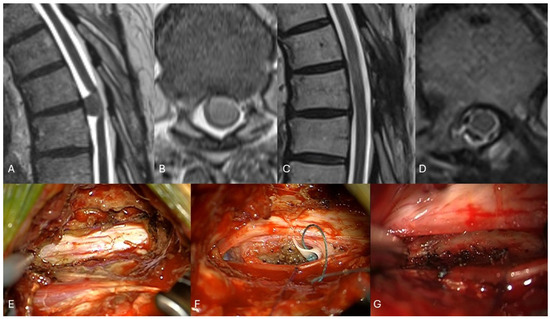

Concomitant Thoracic Spinal Hemangioma and Dural Arteriovenous Fistula: Case Report and Technical Note

Background and Clinical Significance: The coexistence of spinal hemangiomas and dural arteriovenous fistula (SDAVF) is uncommon. Unclear imaging and progressive neurological impairment require early surgical management. Case Presentation: A 76-year-old woman presented with progressive thoracolumbar pain and worsening bladder dysfunction. Magnetic resonance [...] Read more.

Background and Clinical Significance: The coexistence of spinal hemangiomas and dural arteriovenous fistula (SDAVF) is uncommon. Unclear imaging and progressive neurological impairment require early surgical management. Case Presentation: A 76-year-old woman presented with progressive thoracolumbar pain and worsening bladder dysfunction. Magnetic resonance imaging (MRI) of the thoracic spine revealed a round-shape expansive lesion at T11 with spinal cord edema and homogeneous contrast enhancement. Despite a chronic presentation, the subacute progression of bladder dysfunction and spinal cord edema warranted timely intervention. Intraoperatively, a vascular malformation resembling a dural arteriovenous fistula (SDAVF), unrecognized at pre-operative imaging, was found in association, and histological examination confirmed the diagnosis of hemangioma. The mechanism of coexistence remains unclear, although venous hypertension due to fistula could induce vascular malformations. Conclusions: This case emphasizes the importance of thorough imaging, timely intervention and intraoperative assessment in patients presenting with a suspicion of spinal hemangioma; it may also provide awareness of potentially associated concurrent lesions such as SDAVFs, unrecognized at pre-operative imaging, and technical insights during surgery. Full article